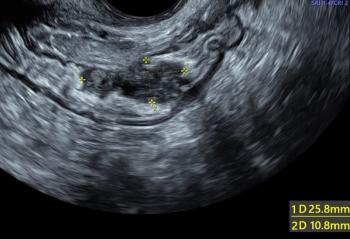

Ultrasound images: Gynecologic diagnoses (Part 1)ByBeryl R. Benacerraf, MDJuly 11th 2019The first slideshow of our gynecologic ultrasound collection reviews commonly missed diagnoses and offers tips for recognizing them on ultrasound.